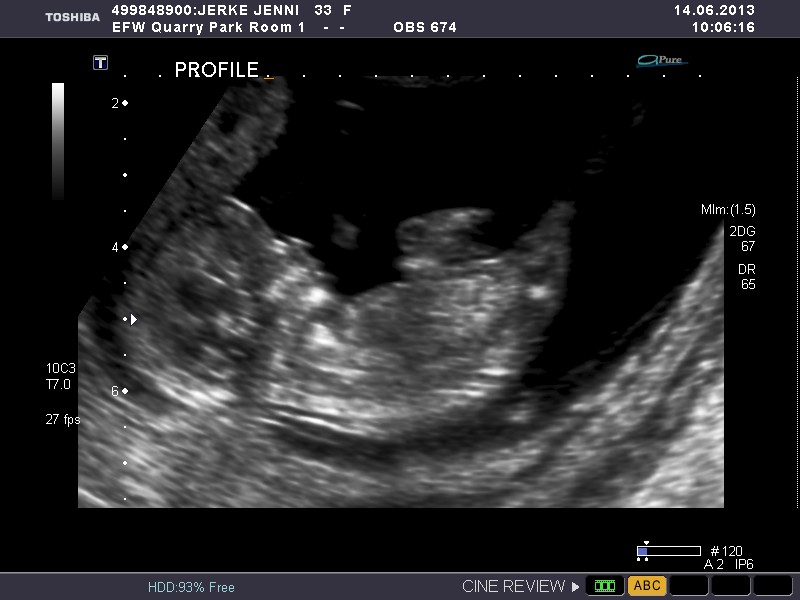

Please give me your best guess as to wether the baby in this ultrasound is a boy or girl.